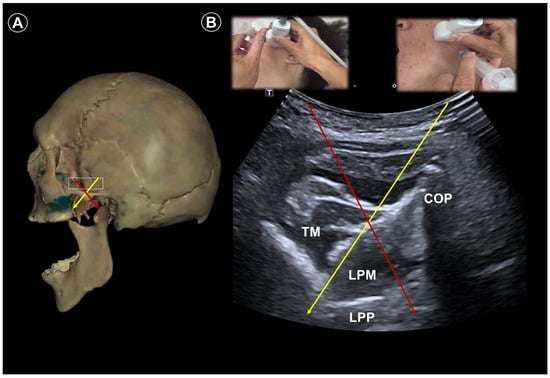

| Trigeminal neuralgia | Paroxysmal facial pain in one or more divisions of the trigeminal nerve | Neurovascular compression at root entry zone | Head neutral | Linear probe, in-plane

| Sustained pain relief by nerve block (case study) | Use Doppler imaging to avoid vascular puncture |

| Lateral, with affected side up | Curvilinear probe, out-of-plane

| |||||